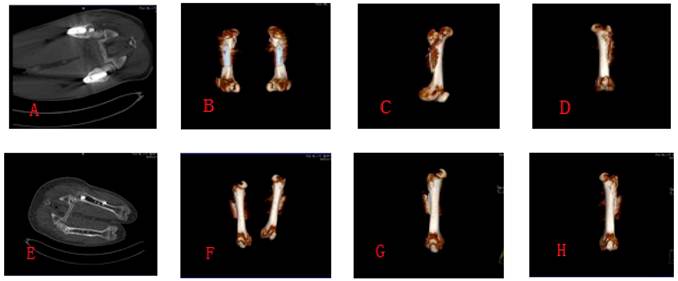

Figure 4

A,B,C,D showed the CT scan photographs at week 8 postoperatively; E,F,G,H showed the CT scan photographs at week 16 postoperatively.

No pigs had postoperative complications and all were able to walk on the 3rd postoperative day and had stable fixation of their femurs at 8 and 16 weeks. At 8 and 16 weeks postoperatively, we assessed the experimental animals by X-rays, CT scans and postmortem visual appraisal of evidence of bone healing (Figures 3, 4, 5).

Eight weeks postoperatively, bone healing according to the Lane-Sandhu score was better in the Hb-DHS than in the DHS group, this difference being statistically significant (Z test −2.530, P < 0.05) (Tables 2 and 3). The Vp and BMD were also significantly better in the Hb-DHS than in the DHS group (Z test −2.337 for Vp, −2.291 for BMD on the tension side and −2.309 for BMD on the pressure side, P < 0.05). Sixteen weeks postoperatively, bone healing according to the Lane-Sandhu score was still significantly better in the Hb-DHS than the DHS group (Z test −2.247, P < 0.05). The Vp and BMD were also significantly better in the Hb-DHS than the DHS group (Z test −2.336 for Vp, −2.247 for BMD on the tension side, −2.309 for BMD on the pressure side, P < 0.05) (Tables 2 and 3).